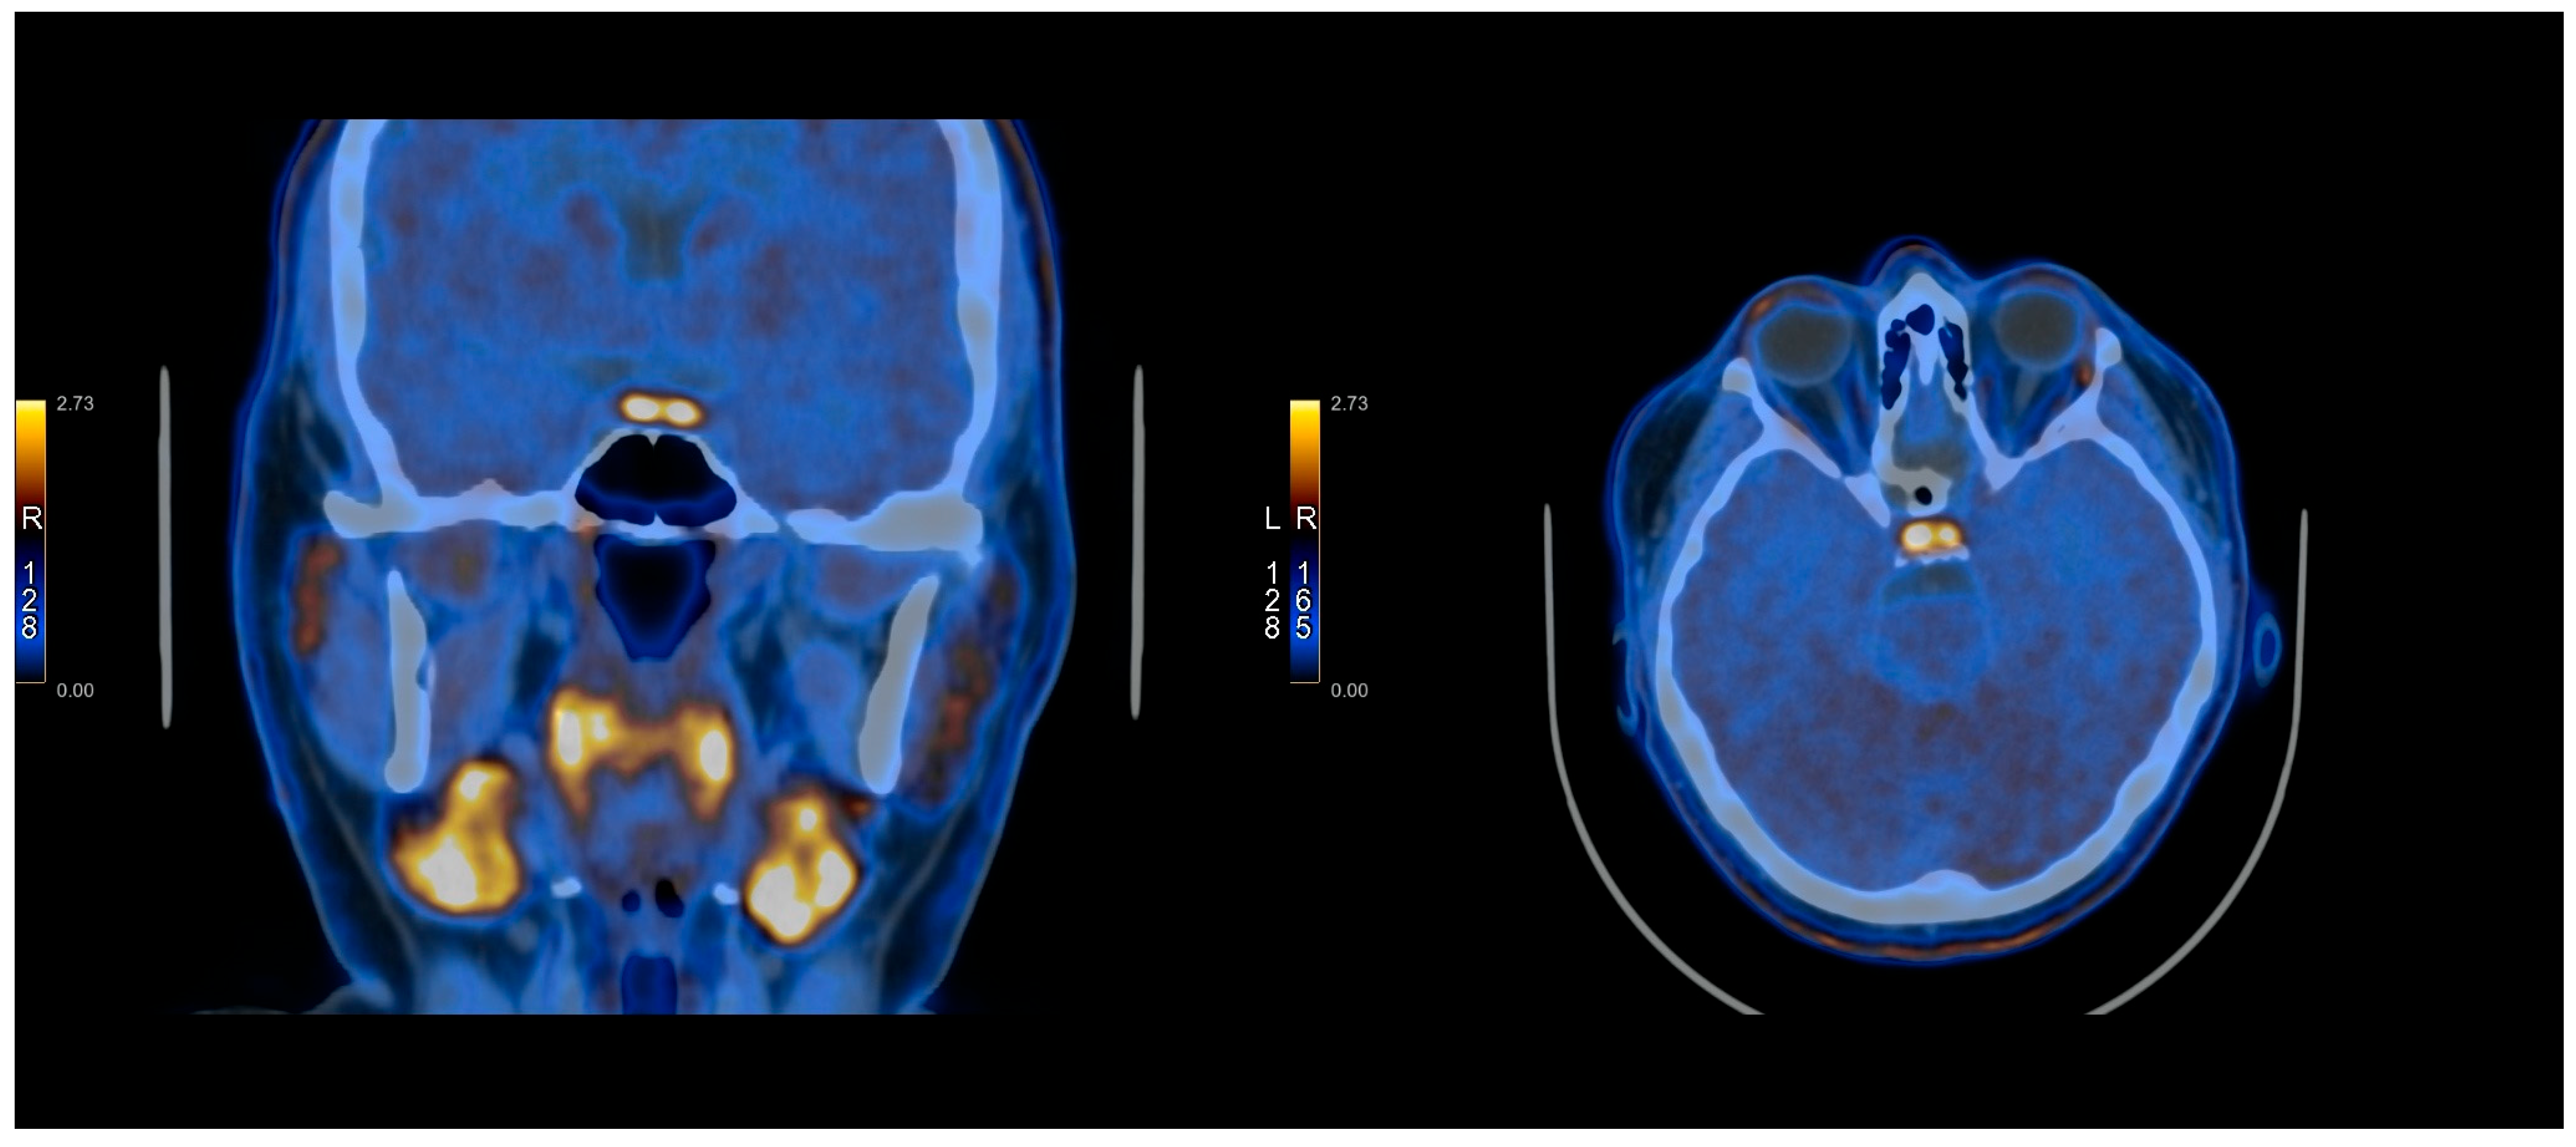

2.3. PET Protocol

2.4. Methionine Protocol